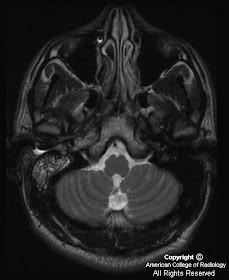

Axial T2. Abnormal high signal in right mastoid air cells and petrous apex (Figure 6).

Post-contrast. There is enhancement within the right petrous apex and mastoid air cells (Figure 7).

Post-contrast. Image at a slightly higher level than prior image demonstrates an enhancing process with extention to the dura of the middle cranial fossa and the prepontine region (Figure 8).